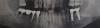

7542 Опубликовано 22 июля, 2013 Поделиться Опубликовано 22 июля, 2013 Всем привет. У меня накрылся мост (нижний), на 4 зуба. Чтобы не утомлять докторов массой подробностейи своих планов относительно него, сначала спрошу о главном а потом уже перейду к вопросу что делать с мостом. Главный вопрос в том, каковы у меня кости нижней челюсти ? Прилагаю два снимка от 2004 года (там слева вы видите ситуацию перед установкой моста, он сделан в конце 2004г ), и снимок 2011 года (там слева вы видите этот мост который к тому времени 5 лет работал отлично, а потом с 2009г начал чуть напрягать подвижностью коронки на 7 опорном зубе). Сравнив эти 2 снимка у меня закралось подозрение что кости теряют свои свойства, что видно как потемнения целых областей в тех местах где не было годами никакой нагрузки. Еще в области одного имплантата вокруг самого шурупавидна тонкая черная каемка, как будто кость у самого винта не такая как везде.Может на другой стороне двойной зуб на имплантах стоит только благодаря тому что коронки сварены вместе, а так вылетел бы ?( Я особо ничего не чувствую, они с 2008 г вкручены а под нагрузкой с 2009, т.е. на снимке им 3 года как вкручены и 2 года с коронками). Но посмотрев снимок 2004г я подозреваю что некоторое разрежение плотности кости уже было на этом месте т.к. там был корень разрушенной нижней шестерки который был проблемным с детства. В 2011 году меня смотрел имплантолог (у него и делался снимок 2011 г.), и ничего про плохие кости не сказал, и даже вкрутил несколько имплантатов в верхнюю челюсть. Но консилиум всяко лучше Второй вопрос в том, как глубоко у меня проходит нерв на нижней челюсти. У меня есть опыт имплантации у 2 докторов, первый мне ставил эти 2 что на фото 2011г видны. Он дольше в этом бизнесе, похоже что опыт и проходимость точки выше.Но ценник радикально выше чем у второго. И тот и другой работают с альфа-био.И тот и другой хирургический шаблон с нормированным углом-направляющей не делают, сверлят "на глазок" .Но первый врач рассчитывал импланты по томограмме КТ, а второй - по панорамному снимку. Если нерв у меня проходит низко, то пойду ко второму. Если высоко и риск просверлить канал нерва большой, то пожалуй лучше не рисковать и идти к тому кто уже на нижнюю челюсть мою ставил импланты. Вот 2 таких вопроса, если ответы на них будут располагать к имплантации, то восстанавливать мост на всю длину 4 зуба не буду, тем более что опорный 7й зуб вылетел вместе с начинкой-вкладкой и в десне 2 дырки в которых два его корня.Второй доктор сказал в 2011 что этот опорный 7й зуб вообще не зуб а просто 2 корня, однако же простоял 8,5 лет мост. Ссылка на комментарий

Mane Опубликовано 23 июля, 2013 Поделиться Опубликовано 23 июля, 2013 Если зубы 44 и 45 естьсмысл сохранять, то там необходимо перелечить каналы, восстановить культю зубов. Покрыть временными коронками. Это пока. В области 46 и 47 нужно планировать 2 имплантата. В области отсутствующего 46 возможен дефицит кости. А в области 47 возможен вариант удаления 47 и установки имплантата в то же посещение. Для прогнозирования сценария, нужен снимок - компьютерная томография. Ссылка на комментарий